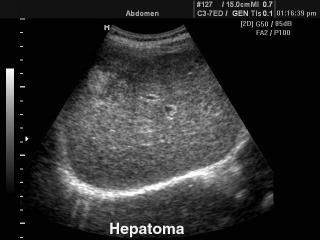

Конвексный датчик C 3-7ED/50/70

Акушерские исследования (плод, сердце плода), гинекология (матка, яичники), абдоминальные исследования (печень, желчный пузырь, поджелудочная железа, селезенка, глубокие сосуды), почки.

Биопсийный набор: есть.